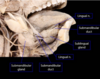

54

label the sublingual and submanibular salivary glands